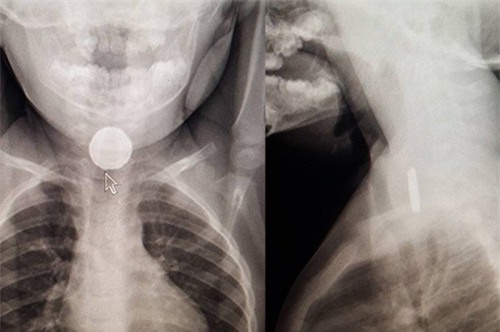

Tại bác sĩ thứ tư, cha mẹ Katie yêu cầu được cho con chụp X-quang. Kết quả cho thấy có một vật nhỏ mắc kẹt trong thực quản cô bé 2 tuổi.

Khi đó, các bác sĩ phát hiện ra nó đã bắt đầu ăn mòn và làm hỏng thực quản của Katie. Viên pin tròn nhỏ nhanh chóng được lấy ra và may mắn, Katie đã phục hồi tốt sau điều trị.